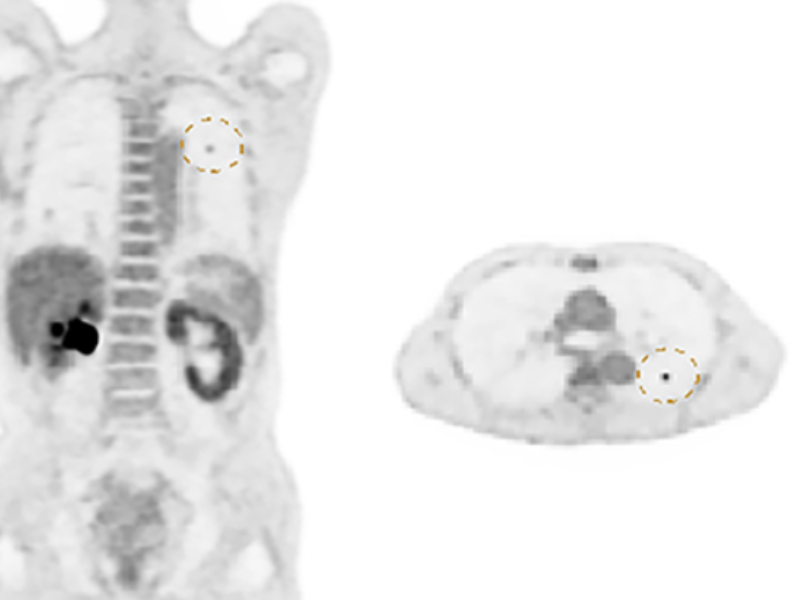

The large 24 cm axial digital PET field of view (FOV) provides exceptional image quality with 2.9 mm NEMA resolution that improves quantitative accuracy and small lesion detectability.

Lesion Detectability for PET